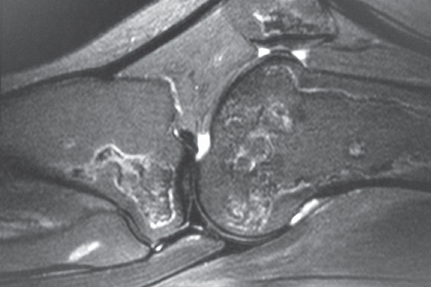

Due to the long-standing nature of the pain MRI of the knee was ordered. T1 and T2 (Figures 3-6) weighted images demonstrate serpiginous areas of increased and decreased signal paralleling each other consistent with the double line sign, which is classic for medullary infarcts of bone.

Figure 4. T2 weighted image in the sagittal plane.